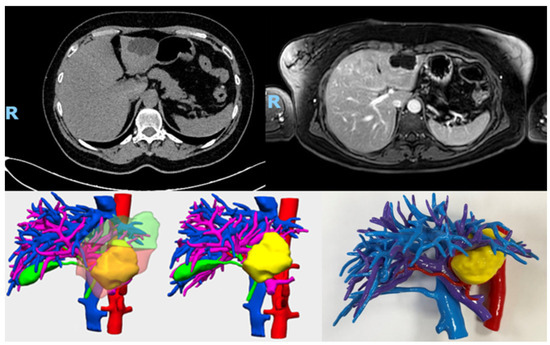

Three-Dimensional Models in Hepatic Surgery: Clinical Outcomes A Single-Center Experience

Background: Hepatic resection requires precise knowledge of vascular anatomy and remnant liver volume to guarantee both safety and efficacy. Three-dimensional (3D) models, either virtual or printed, have been proposed as tools to optimize surgical planning, education, and intraoperative navigation. Material and Methods: This [...] Read more.

Background: Hepatic resection requires precise knowledge of vascular anatomy and remnant liver volume to guarantee both safety and efficacy. Three-dimensional (3D) models, either virtual or printed, have been proposed as tools to optimize surgical planning, education, and intraoperative navigation. Material and Methods: This retrospective observational study evaluated the impact of 3D model utilization (virtual and printed), in 89 patients who underwent elective hepatectomy at Infanta Elena University Hospital (Valdemoro, Madrid, Spain) between May 2018 and May 2023. The implementation of 3D modeling began to be routinely implemented as of November 2020. Patients were divided into two groups: those without 3D modeling (n = 40) and those with 3D modeling (n = 49). Results: Baseline characteristics were comparable between groups. Intraoperative blood loss was significantly lower in the 3D model group (median 175 mL vs. 262.5 mL; p < 0.001), with no statistically significant differences in operative time, complication rate (Clavien–Dindo classification), length of hospital stay, or in-hospital mortality. Multivariable analysis identified dyslipidemia, postoperative sodium delta, and postoperative increase in direct bilirubin as independent risk factors for complications, whereas albumin demonstrated a protective effect. Conclusions: Three-dimensional modeling improves anatomic orientation and reduces intraoperative blood loss, although it does not significantly modify classic perioperative outcomes. Its principal value appears to reside in preoperative planning and technical safety rather than direct clinical impact. Full article

(This article belongs to the Section General Surgery)

Show Figures

Figure 1